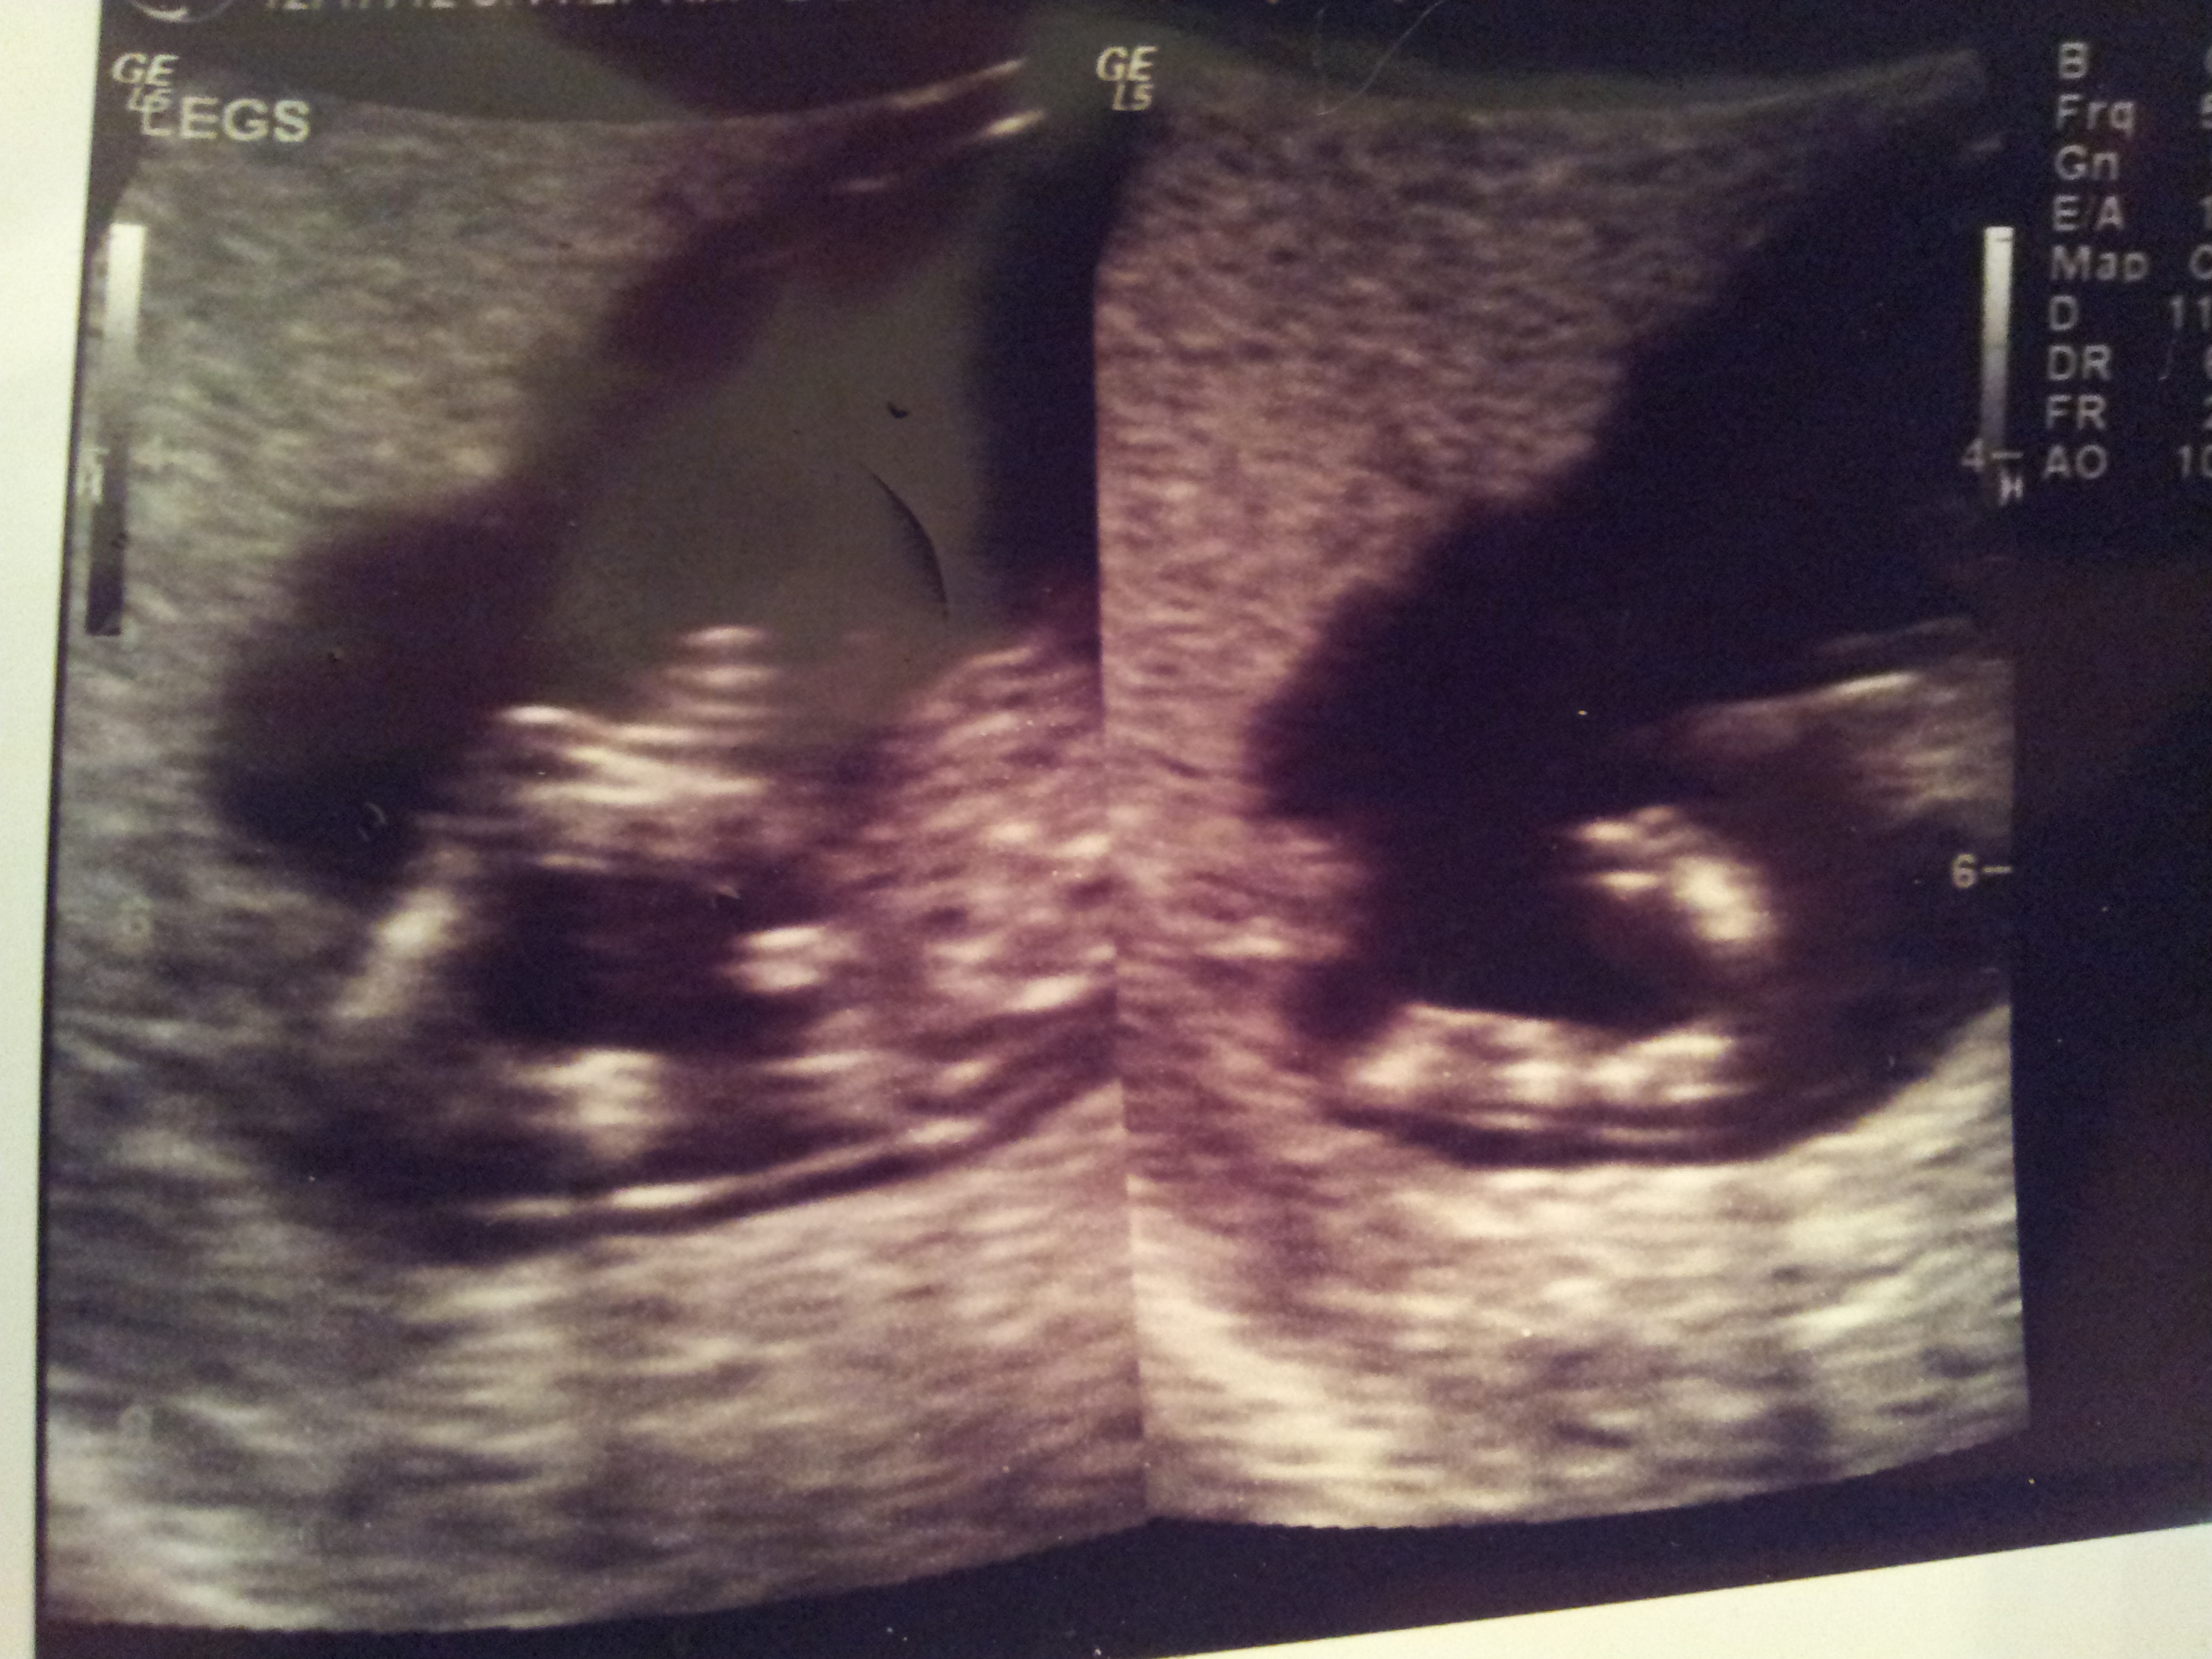

OK so has anyone had a nub shot at 13 weeks and it turn out to be a girl? I have a nub shot but it isnt a side profile its straight on between the legs. Im just curious if its still possible for my baby to be a girl or if its a definite boy...?

Attachment 8574